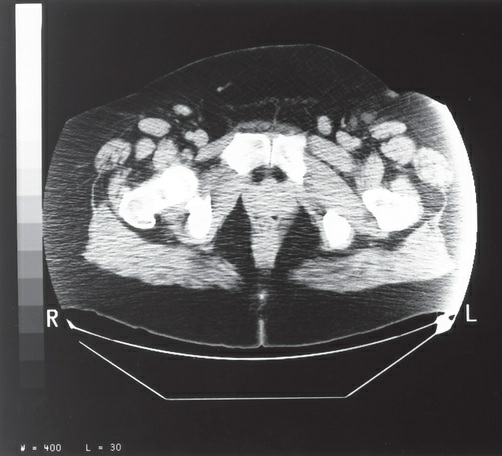

The artifact present on the lateral borders of the image in the

figure most likely represents which of the following?

a. edge gradient

b. out-of-field artifact

c. tube arcing

d. beam hardening

out-of-field artifact

The image in the figure was produced using the following

parameters: large (full) scan field of view (SFOV); maximum

display field of view (DFOV) (48 cm); 200 mA, 120 kVp; soft

tissue algorithm. Which of the following technical adjustments

would serve to reduce the artifact present?

a. switching to a detail or bone algorithm

b. using a smaller SFOV

c. increasing the mA to 240 and the kVp to 140

d. centering the patient within the SFOV

centering the patient within the SFOV